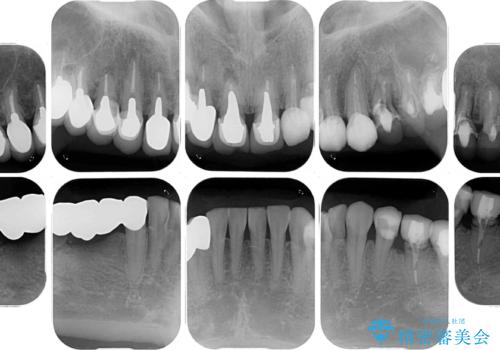

- 以前治療した歯が欠けたり、痛みを感じたりしているとのことで来院された患者様です。

アメリカ国内を転々としながら治療を行ったため治療跡がモザイク様で、クラウンが壊れていたり、抜歯が必要であったりしていました。

上下左右すべての奥歯に処置が必要であり、同時に行うと食事が取りにくくなってしまったり、手前の歯に負担がかかって初診時よりも状況が悪化したりする可能性があるため、片方ずつ処置を進めて行くこととしました。

下顎右側は骨造成を併用してインプラント治療を行い、その他の奥歯もインプラントや歯周外科処置を併用して補綴治療を進め、最後に前歯部の欠けてしまったセラミッククラウンを作り替えることとしました。